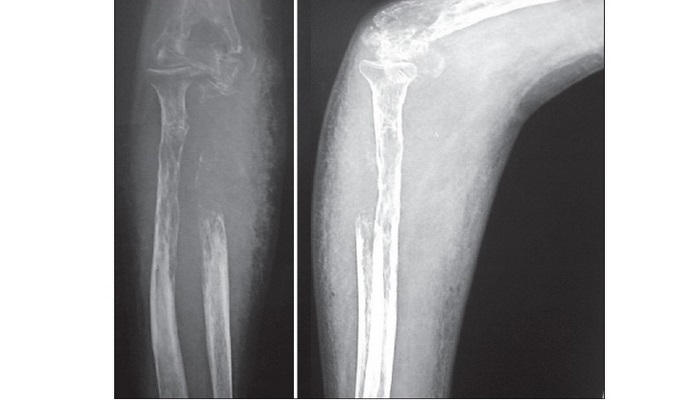

Рентгеновский снимок с частично "исчезнувшей" костью

В марте 2018 года в медицинском журнале "BMJ Case Reports" появился уникальный материал от врачей королевской больницы Эдинбурга - история наблюдении развития синдрома исчезающих костей у неназванной 44-летней женщины - жительницы Шотландии. Все началось с того, что женщину стали мучить учащающиеся боли в ее левом плече. Потом ей стало сложно двигать этой рукой. Когда она обратилась в больницу, у нее сначала заподозрили рак, однако две последующие биопсии ничего не показали. Лишь третья биопсия выявила аномалию и это оказалось разрастание кровеносных сосудов в районе плечевой кости. За последующие месяцы у женщины увеличивались боли, рука опухла, разрасталась сосудистая ткань и одновременно разрушалась костная ткань. И лишь спустя 18 месяцев, когда кость на рентгеновских снимках стала почти не видна, врачи поняли, что имеют дело с синдромом исчезающей кости. На представленных ниже рентгеновских снимках хорошо видно как постепенно пропадала плечевая кость пациентки. На последнем снимке кость уже не видна и ее место заняла разросшаяся сеть тонких кровеносных сосудов.